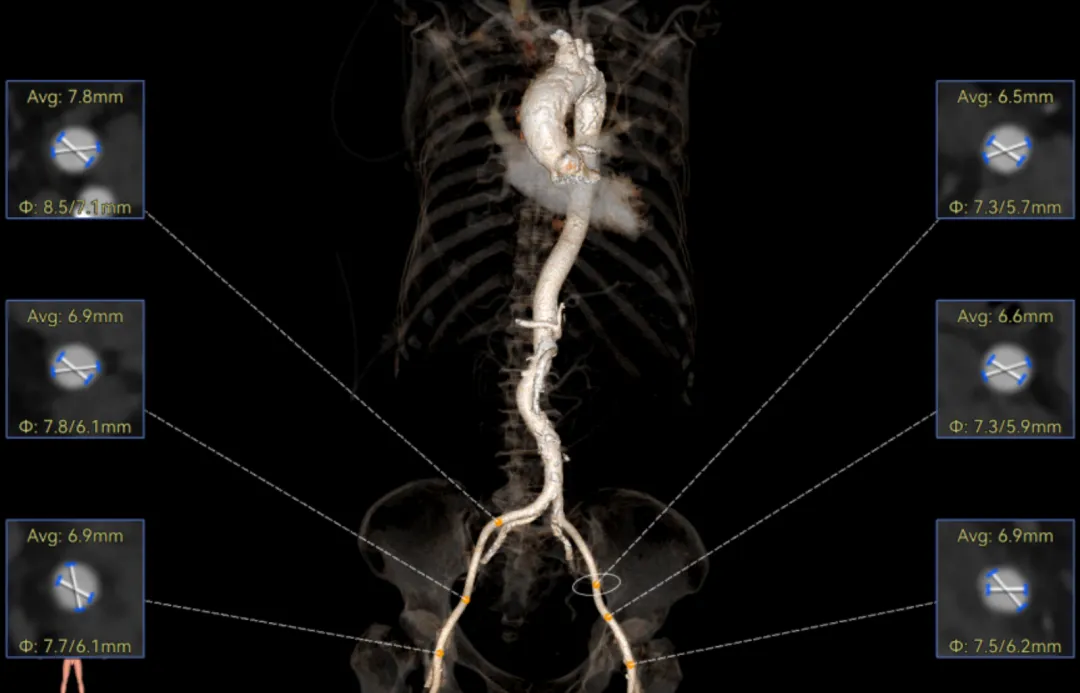

外周双侧入路无明显迂曲、直径可容纳20F大鞘通过,双侧中分叉,穿刺需注意。主动脉弓角弓距可,髂总动脉及分支多处钙化,瓷化升主动脉,钙化由升主动脉蔓延至主动脉弓侧壁及弓顶弓底部,有一定卒中和夹层风险。

经过庄晓东教授团队分析,拟右股动脉作为主入路,使用可调弯长鞘建立通道,使用18mm球囊预扩,选择AV23号Prostyle A®瓣膜进行释放。